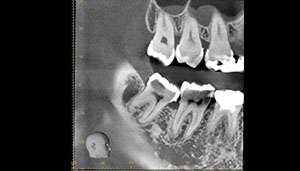

CT

- Before

- After

CTで親知らずと神経(下歯槽管)の位置を確認しました。

親知らずと神経は一定の距離があり、麻痺などのリスクがほとんどないと判断できます。

半埋伏の親知らずでした。3糸縫合しました。